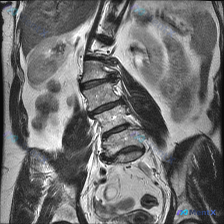

整理到一张腰椎及腹部区域的 MRI 冠状位 T2 加权图像,先不发结论,只放核心影像表现: 核心影像表现 1. 脊柱序列:腰椎向右侧明显侧弯; 2. 椎间盘:所有观察到的腰椎间盘在 T2WI 上均呈信号减低(黑盘征),提示多节段脱水/变性;部分椎间隙左右高度不一致; 3. 骨质与软组织:冠状面未见明...